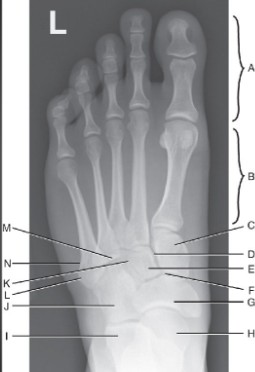

What does C represent in this foot image?

medial cuneiform

What does E-I represent in this image?

intermediate cuneiform, navicular cuneiform joint, navicular, talus, calcaneus

What does J-M represent in this foot image?

cuboid, lateral cuneiform, 5th metatarsal tuberosity, 5th metatarsal base, 4th tarsometatarsal joint